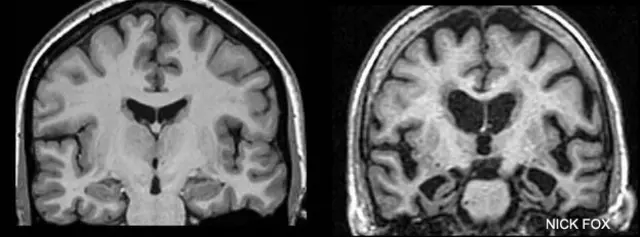

"Estas familias nos ofrecen información muy valiosa sobre los primeros cambios que suceden en el cerebro, incluso antes de que aparezcan los síntomas", explica Nick Fox, investigador de UCL.

Para eso realizan escáneres de su cerebro que rastrean la progresión de la enfermedad.

Graham también debe hacer pruebas de memoria y se le han practicado punciones lumbares para extraer fluido y así detectar proteínas dañinas en el líquido cefalorraquídeo.